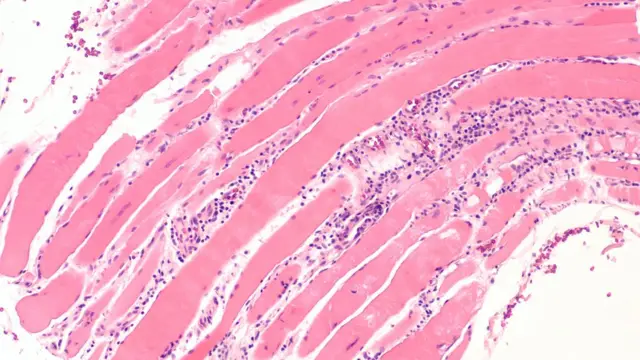

दुखावलेल्या स्नायूंसाठी रक्ताची तपासणी, शरीरात किती प्रमाणात आलेली सूज याची चाचणी तसंच शरीरात किती अँटीबॉडीज आहेत याची चाचणी करून मायोसायटिसचं निदान करता येऊ शकतं. त्यासाठी इलेक्ट्रोमायोग्राफी, मसल बायोप्सी, जेनेटिक टेस्टिंग अशा चाचण्या उपलब्ध आहेत.